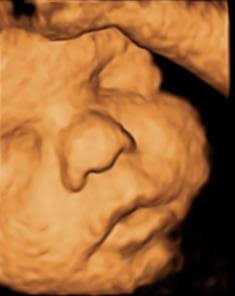

בדיקה זו היא ללא ספק מבין הבדיקות המרגשות שיש בהריון. בשלב זה העובר מודגם בצורה ברורה וניתן להבחין בפניו ובגופו בצורה מוחשית.